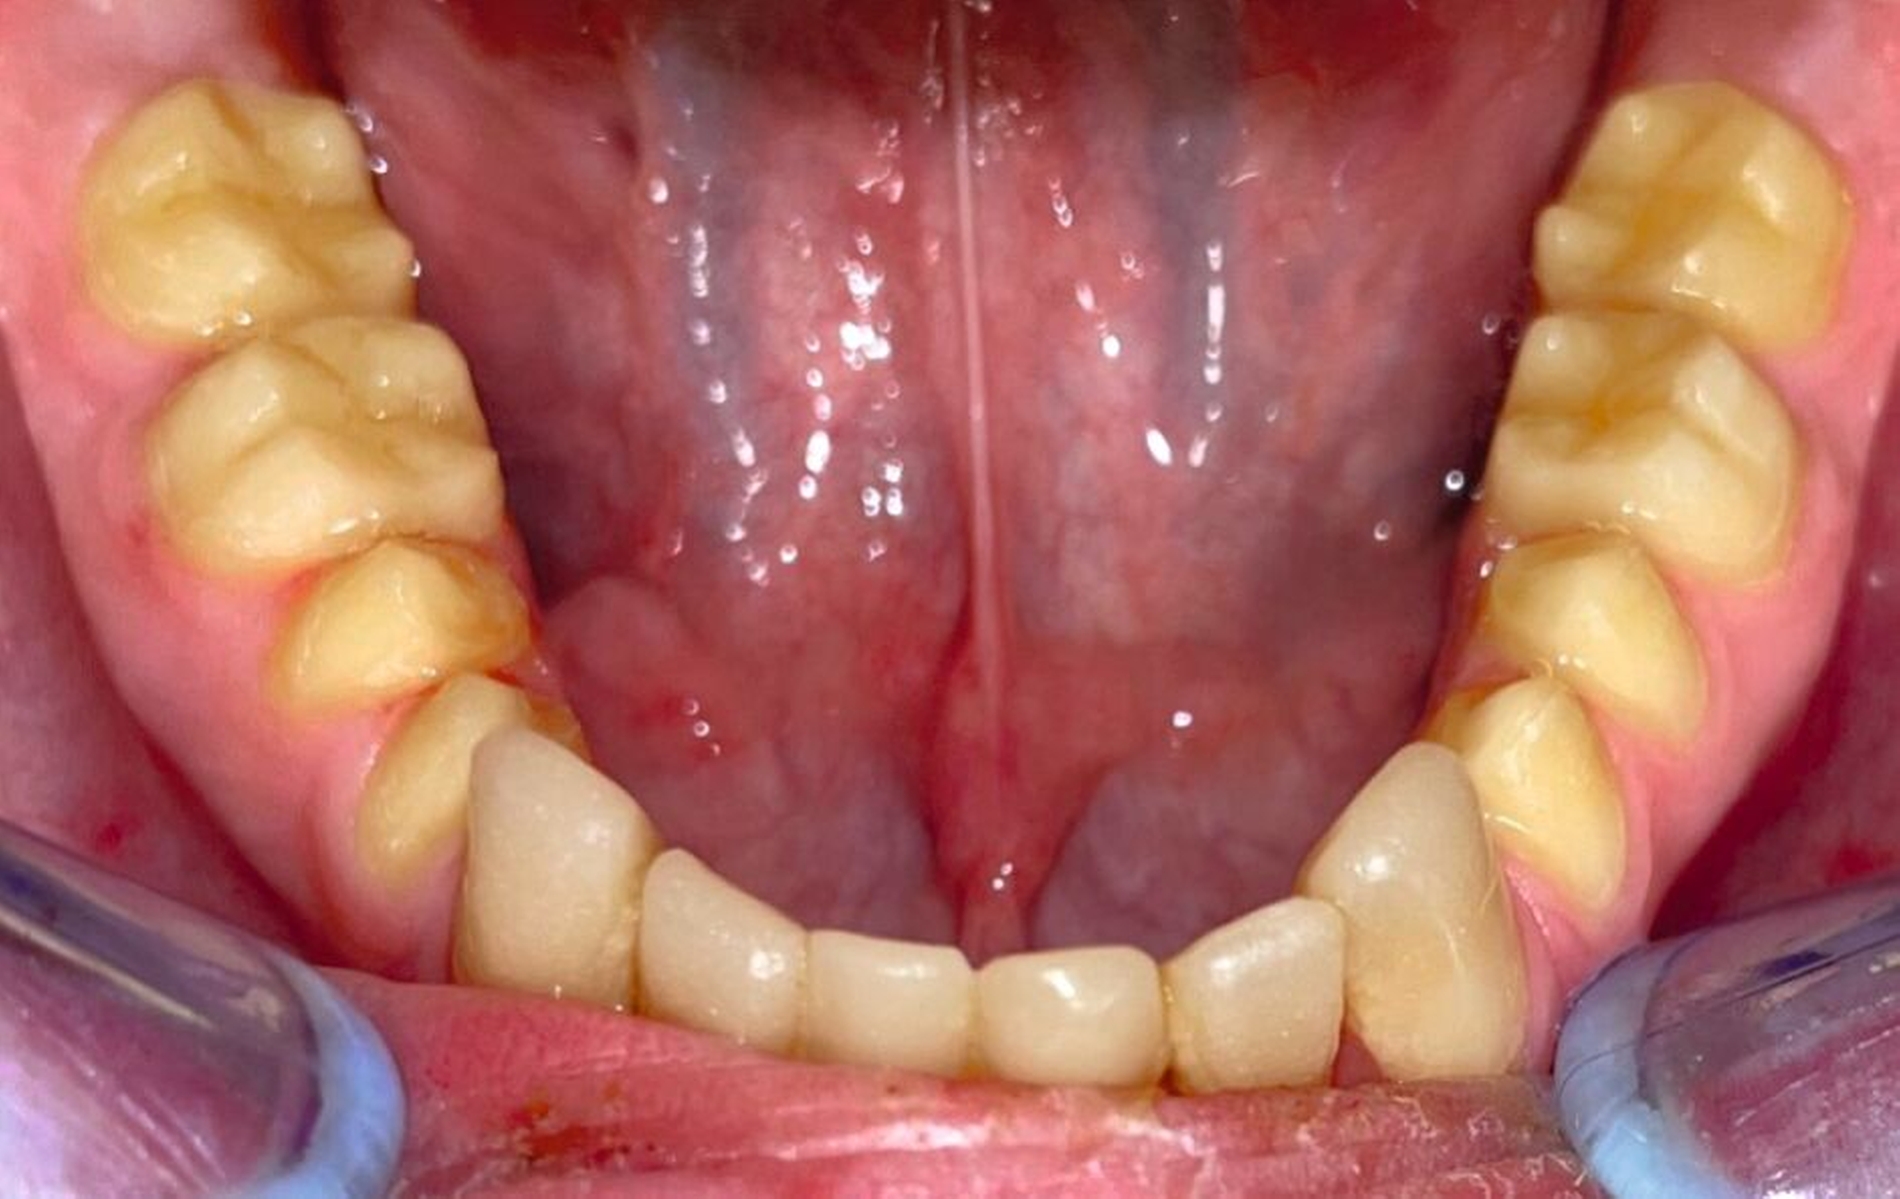

Klinisch zeigte sich ein kariöses Wechselgebiss mit generalisierten Verfärbungen und rauer Schmelzoberfläche. Mehrere Milch- und bleibende Zähne wiesen aktive kariöse Läsionen auf. Zahn 64 war zusätzlich druckdolent und gelockert, mit einer vestibulären Schwellung der Gingiva. Zudem bestanden eine Mittellinienabweichung, ein Overbite von vier Millimetern und ein Overjet von elf Millimetern (Abbildung 1). Extraoral fiel ein fliehendes Kinn mit inkomplettem Lippenschluss und hyperaktivem Musculus mentalis auf. Röntgenologisch waren alle Zähne angelegt, der Zahnschmelz zeigte jedoch eine reduzierte Opazität (Abbildung 2). Eine genetische Abklärung wurde von den Erziehungsberechtigten aus ethischen Gründen abgelehnt.

Klinisch zeigten sich ein nicht-kariöses Wechselgebiss mit generalisierter Schmelzhypoplasie an allen Zähnen sowie eine insuffiziente Mundhygiene. Zusätzlich bestanden eine fehlende Mittellinienübereinstimmung, ein Overbite von minus vier Millimetern und ein Overjet von sechs Millimetern (Abbildung 5), die sich phonetisch in einem interdentalen Sigmatismus äußerten. Röntgenologisch waren alle Zähne angelegt, jedoch war der Zahnschmelz stark reduziert oder vollständig fehlend (Abbildung 6).